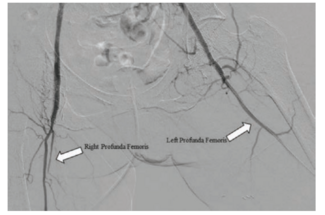

In the case herein, procedural success — defined by stenosis reduction and distal reperfusion of bilateral stumps — was dependent upon gaining arterial access through exotic techniques and crossing the CTOs.